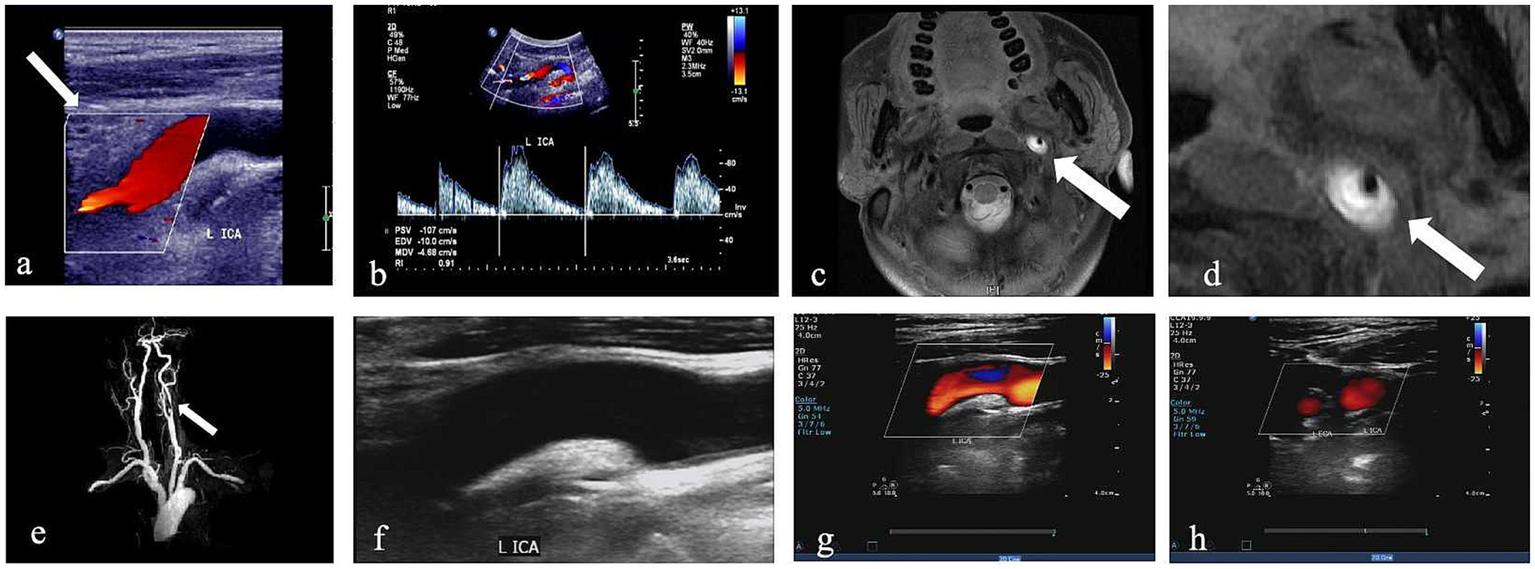

Figure 2

CDU imaging for one patient with left internal CAD. (a,b) Greyscale and pulsed-wave Doppler with hypoechogenic intramural hematoma (white arrow) and lumen narrowing. (c,d) Corresponding HRMRI with evidence of a crescent-shape hyperintense on axial FS-T2W images and enlarged view of FS-T2W (white arrow). (e) 3D time-of-flight (TOF) magnetic resonance angiography imaging. (f–h) CDU done 6 months later shows recanalization after treatment; the wall structure of the ICA returned to normal, and the blood flow signal was completely filled.